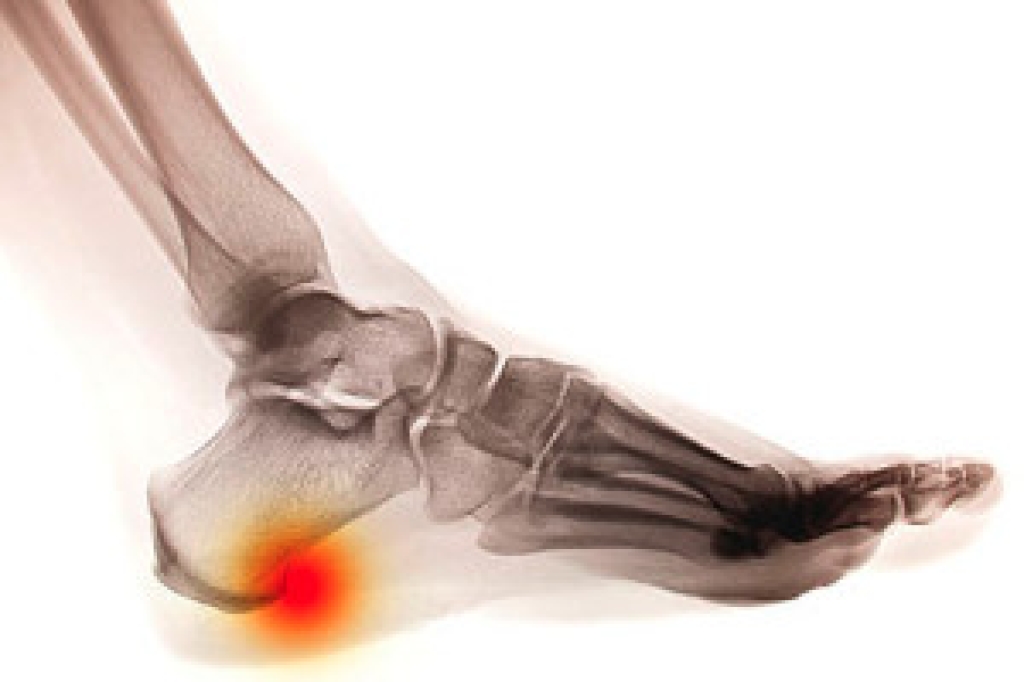

Are Heel Spurs Painful?

The medical condition that is known as a heel spur can develop from standing on hard surfaces for the majority of the day, or from running and participating in jumping activities. It is defined as a bony growth that forms as a result of heel stress, and develops on the heel bone. Some patients experience severe pain and discomfort from heel spurs. Mild relief may be found when correct treatment is started. This can consist of wearing arch supports, performing specific stretches that can help strengthen the heel, or wearing shoes that have adequate cushioning. If you have developed a heel spur, it is strongly advised that you consult with a podiatrist who can properly treat heel spurs.

Heels Spurs

Heel spurs are formed by calcium deposits on the back of the foot where the heel is. This can also be caused by small fragments of bone breaking off one section of the foot, attaching onto the back of the foot. Heel spurs can also be bone growth on the back of the foot and may grow in the direction of the arch of the foot.

Older individuals usually suffer from heel spurs and pain sometimes intensifies with age. One of the main condition's spurs are related to is plantar fasciitis.

Pain

The pain associated with spurs is often because of weight placed on the feet. When someone is walking, their entire weight is concentrated on the feet. Bone spurs then have the tendency to affect other bones and tissues around the foot. As the pain continues, the feet will become tender and sensitive over time.

Treatments

There are many ways to treat heel spurs. If one is suffering from heel spurs in conjunction with pain, there are several methods for healing. Medication, surgery, and herbal care are some options.